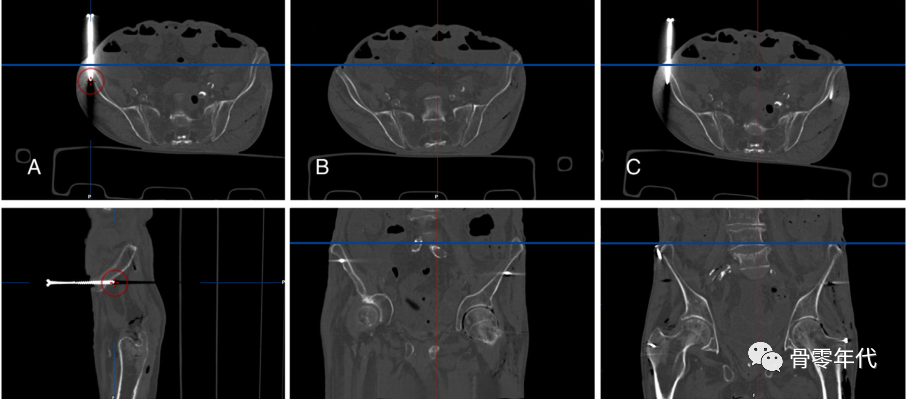

(A)对CT测量,确定了基准地标。然后分析骨盆旋转(B),测量LL、GO和FO的变化(C)。

采用基准点三维ct测量LL (A)、GO (B)和FO (C)变化。对于LL,指小转子上侧面通过ASIS到横平面的距离。从耻骨结节到股轴的垂直距离定义了GO。对于FO测量,创建了Sariali等人描述的特定股骨框架